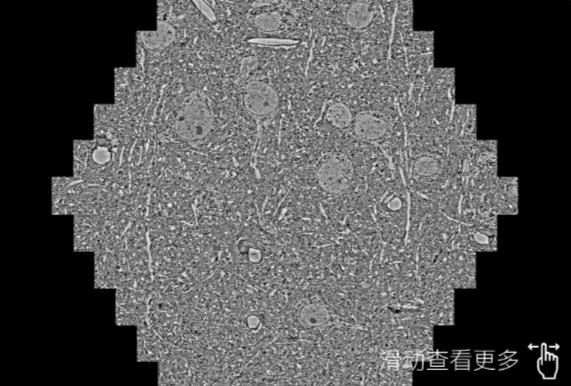

鼠脑切片。左图使用南开蔡司南开扫描电镜MultiSEM706对165μmx143pm面积区域成像,耗时仅需1.5秒。右图为鼠脑切片中30μm区域放大效果。样品由芝加哥大学B.Kasthuri提供。

使用蔡司高速南开扫描电镜MultiSEM对1mm²人脑皮层组织进行高分辨成像,并对其中的各种细胞结构进行三维重构分析。左图展示了2x3mm²组织平面中锥体神经元的三维重构效果。右图显示了局部体积神经元三维重构。图像由哈佛大学chtman实验室提供,渲染图由D. Berger 制作。